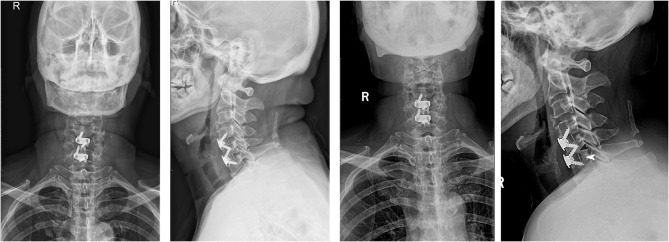

Purpose: The aim of this study was to explore short-term radiological findings after contiguous two-level ACDF with Zero-P VA devices.

Methods: Patients who underwent contiguous two-level anterior cervical discectomy and fusion (ACDF) from C3 to C7 with a Zero-P VA system were followed. Cervical anteroposterior and lateral X-rays and functional outcomes were assessed 3 months after surgery.

Results: Overall, 34.9% of patients had prosthesis subsidence and 74.6% screw loosening. Up to 46.8% of the patients with screw loosening also experienced prosthesis subsidence compared with 0 patients without screw loosening (p=0.0005). The screw-loosening rate was 91.7% in patients with poor positioning of the screw/cage and 70.6% in patients without poor positioning of the screw/cage, but no statistical difference was found between the groups (p=0.267). The subsidence rate was 50% in patients with poor positioning of the screw/cage and 31.4% in patients without poor positioning of the screw/cage, but no statistical difference was found between the groups (p=0.314). VAS scores of patients with prosthesis subsidence were much higher than those without (p=0.031), but this difference was not found for patients with or without screw loosening (p=0.116). The NDI scale was much higher in patients regradless of screw loosening or subsidence.

Conclusion: Screw loosening and prosthesis subsidence happen frequently after contiguous two-level ACDF with Zero-P VA. Screw loosening seems to be the only risk factor for prosthesis subsidence.